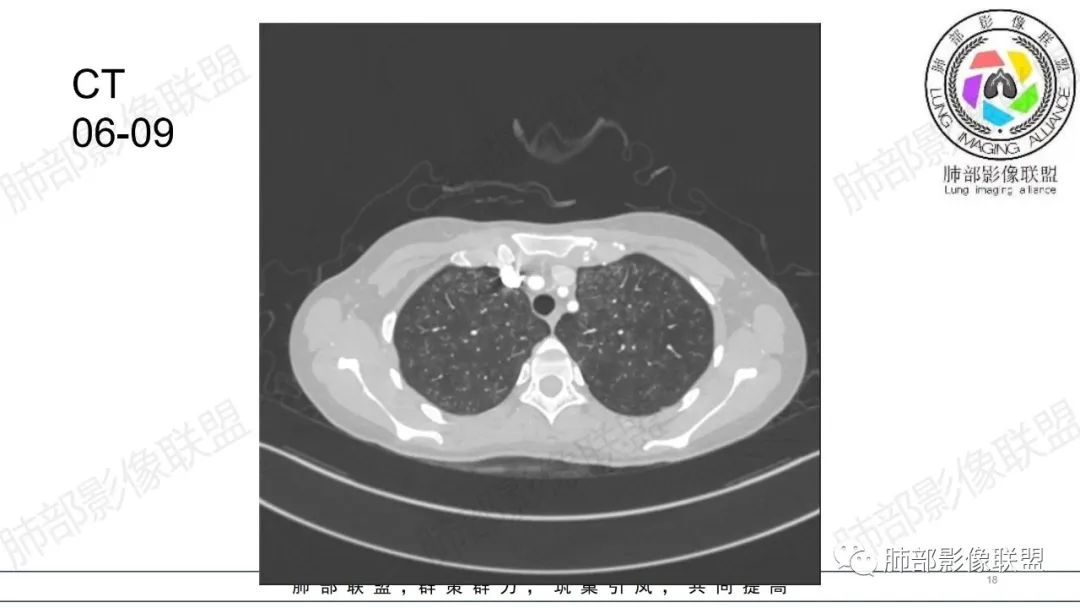

34岁女性患者,“哮喘”病史30年,近期有可疑刺激性气体吸入史;因乏力半年,咳嗽、憋气、发热4天就诊;6.1CT提示双肺广泛毛玻璃影及粟粒样结节,胸膜下闲置及血管周闲置,可见树丫征,部分小叶间隔增厚。考虑:1.过敏性肺泡炎,有可疑刺激气体接触史,胸膜下闲置,广泛毛玻璃影,地图样分布,粟粒结节边界模糊,支持过敏性肺泡炎,但糖皮激素治疗效果不佳,且动态复查血常规血红蛋白进行性降低,过敏性肺泡炎 不符合;2.肺含铁血黄素沉积症:患者30“哮喘”病史,可能为肺含铁症状,肺部CT提示双肺弥漫毛玻璃影及粟粒结节影,中下肺明显,肺底部分小叶间隔增厚,近期咳嗽、憋气、发热,血常规血红蛋白进行性下降,考虑肺含铁急性期症状,但临床无咯血症状,肺含铁不典型。综合考虑:肺含铁血黄素沉积症>过敏性肺泡炎。

年轻女性 ,急性喘息发热,肺部影像弥漫磨玻璃密度,部分细小腺泡结节,胸膜下黑线显示,短期复查,病变密度增高,下肺明显,血管周围肺组织累及较少、且逐渐成小叶间隔分布。考虑弥漫肺泡内病变,并经淋巴道转移,下肺比上肺明显,多为免疫细胞功能下肺较强。1.过敏性肺泡炎,有相关病史,三层密度特点、头尾测分布,符合。2 肺泡微石症,多有钙化,且缓慢起病,病程不太符合,放待排。3 吸入相关肺损伤,有病史,疾病演变过程也符合渗出-肉芽肿改变,建议详细询问病史。4 感染性病变,结核?病变气道分布为主,如此弥漫且没有树丫不符合。5.巨细胞病毒,可以磨玻璃 结节 改变,没有免疫缺陷病史。最后考虑吸入所致 1过敏性肺泡炎、吸入性肺损伤 鉴别肺泡微石症。